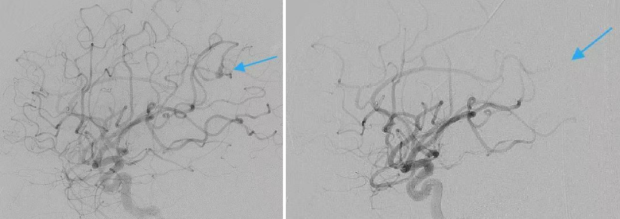

可小金等不了了。“他的心臟問題得爭分奪秒。神外就要想辦法配合。”在3D立體成像技術幫助下,趙元立等人精準找到小金右側大腦中動脈頂支中央溝動脈的動脈瘤,成功將其栓塞。

栓塞治療前動脈造影可見感染性顱內動脈瘤(左圖);栓塞治療後動脈瘤消失(右圖)/圖源:受訪者